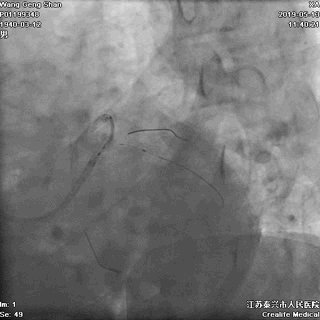

01 导丝进前三叉分支

02 处理LAD中段病变

对角支导丝到位

左冠共计5根导丝